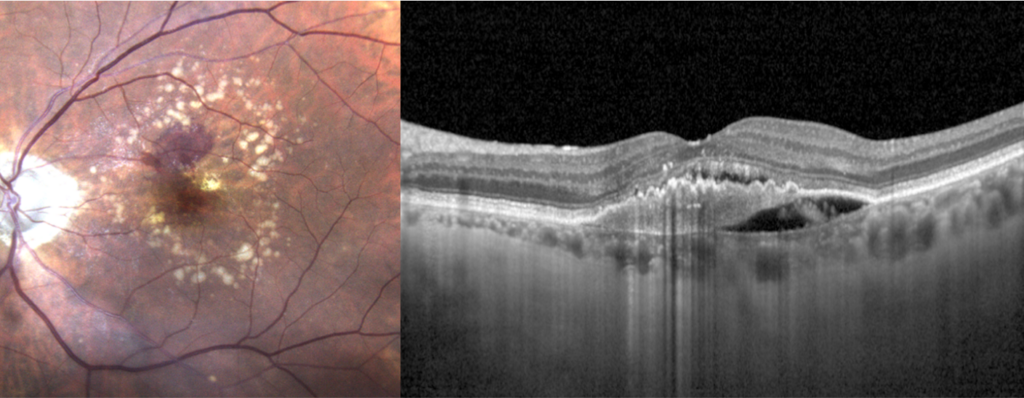

Rétinophoto couleurs montrant une DMLA exsudative avec une hémorragie maculaire et des drusen. Coupe OCT centrée sur la macula avec un œdème et des signes d’exsudation